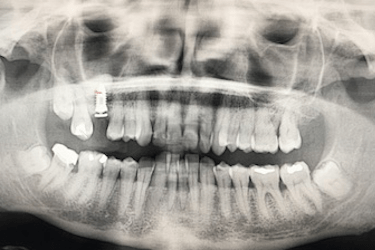

Caso de implantes dentales sin hueso suficiente y regeneración ósea

Paciente real del Dr. Ferrer que presenta la ausencia de una pieza dental.

Al no haber sustituido el diente perdido se ha producido una reabsorción ósea que ha provocado una disminución de la altura del hueso maxilar.

Antes del injerto de hueso dental solo había una altura de 5 mm para colocar el implante.

Para que el especialista pueda colocar un implante dental de forma estable y segura, es necesario una altura de hueso maxilar de al menos 8 – 10 mm.

El mismo día de la cirugía el implantólogo realiza una elevación del seno maxilar y posterior injerto de hueso dental artificial.

El odontólogo levanta la membrana del seno maxilar para introducir del material de relleno que aumentará la cantidad y la calidad del hueso del paciente.

Después de la osteointegración del implante, el paciente acude a revisión para ver el estado del hueso artificial injertado.

La altura del hueso maxilar es ahora de 15 mm lo que ha permitido la colocación del implante dental con poco hueso inicialmente.